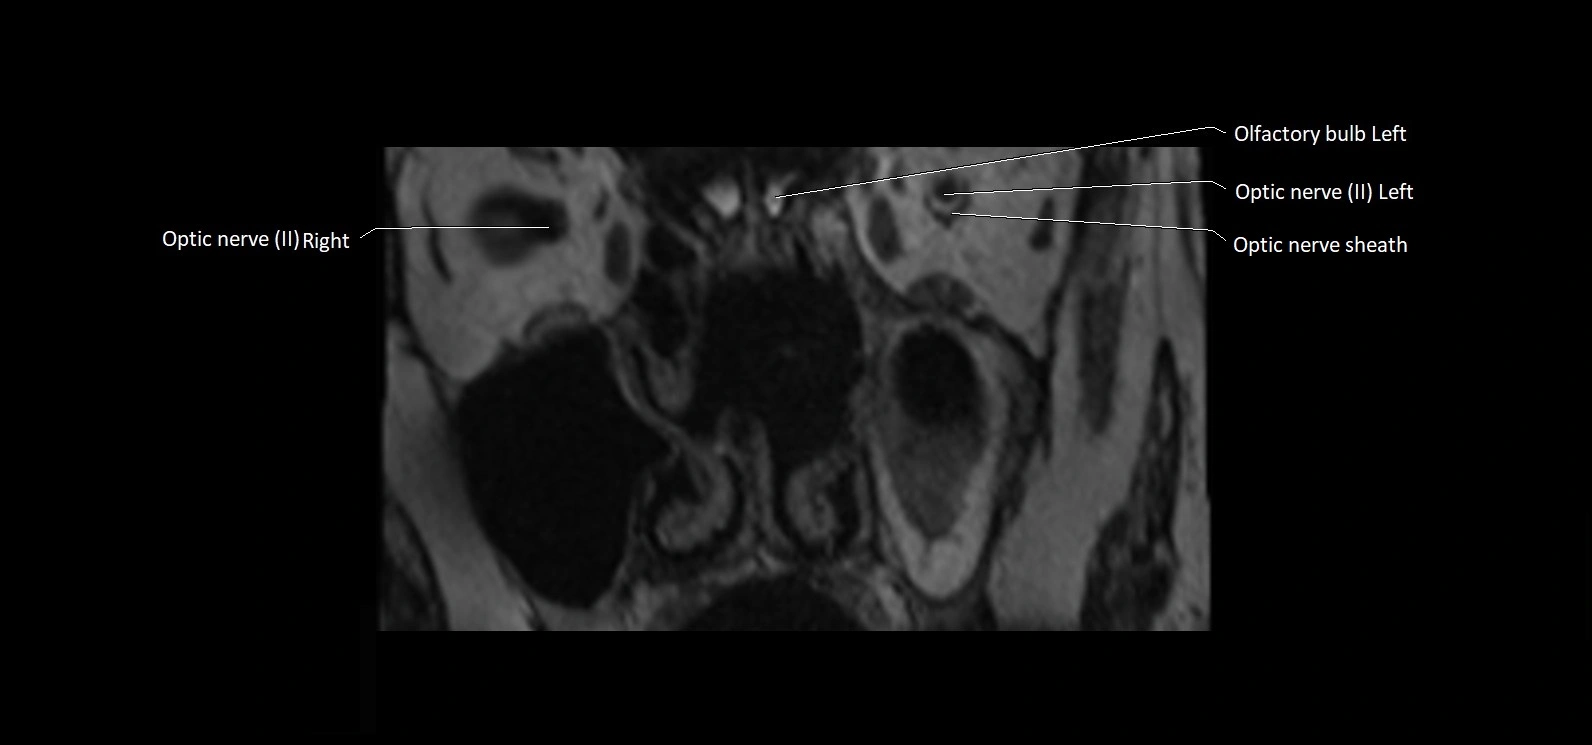

• The abducens nerve is a small, thin, linear structure

• Best visualized on high-resolution T2-weighted 3D MRI sequences (e.g., FIESTA or CISS)

• Seen as a hypointense (dark) line running from the brainstem at the pontomedullary junction, traversing the prepontine cistern, and entering Dorello’s canal under the petrosphenoidal ligament, then into the cavernous sinus, and finally the orbit

• May be challenging to visualize in standard MRI due to its small size

• Pathology may be inferred by absence, displacement, or enhancement of the nerve